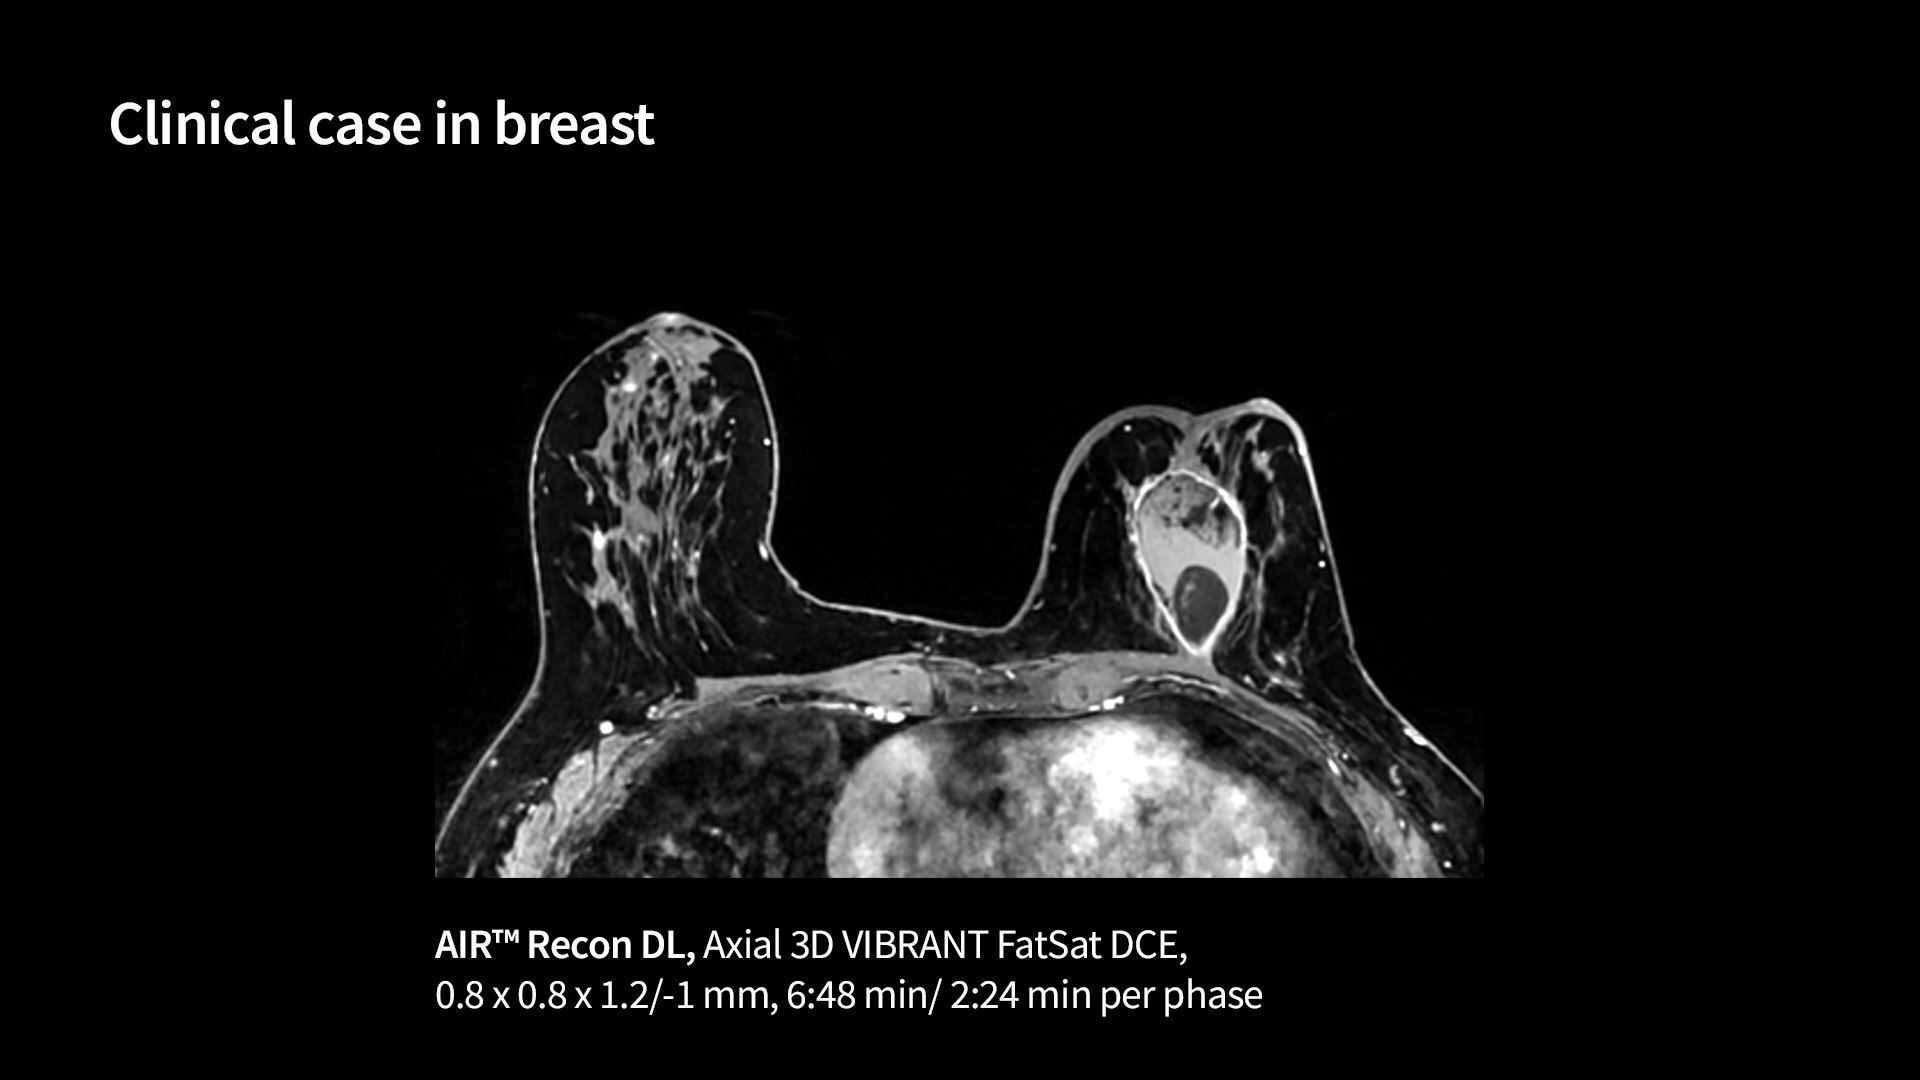

Precision and personalization

Vibrant-and-VibrantFlex1040-x-585

Read case study ico-caret-right

MR image reconstruction with AIR™ Recon DL

AIR™ Recon DL has revolutionized MR imaging with deep-learning based image reconstruction increased image quality, reduced scan time and improved SNR.